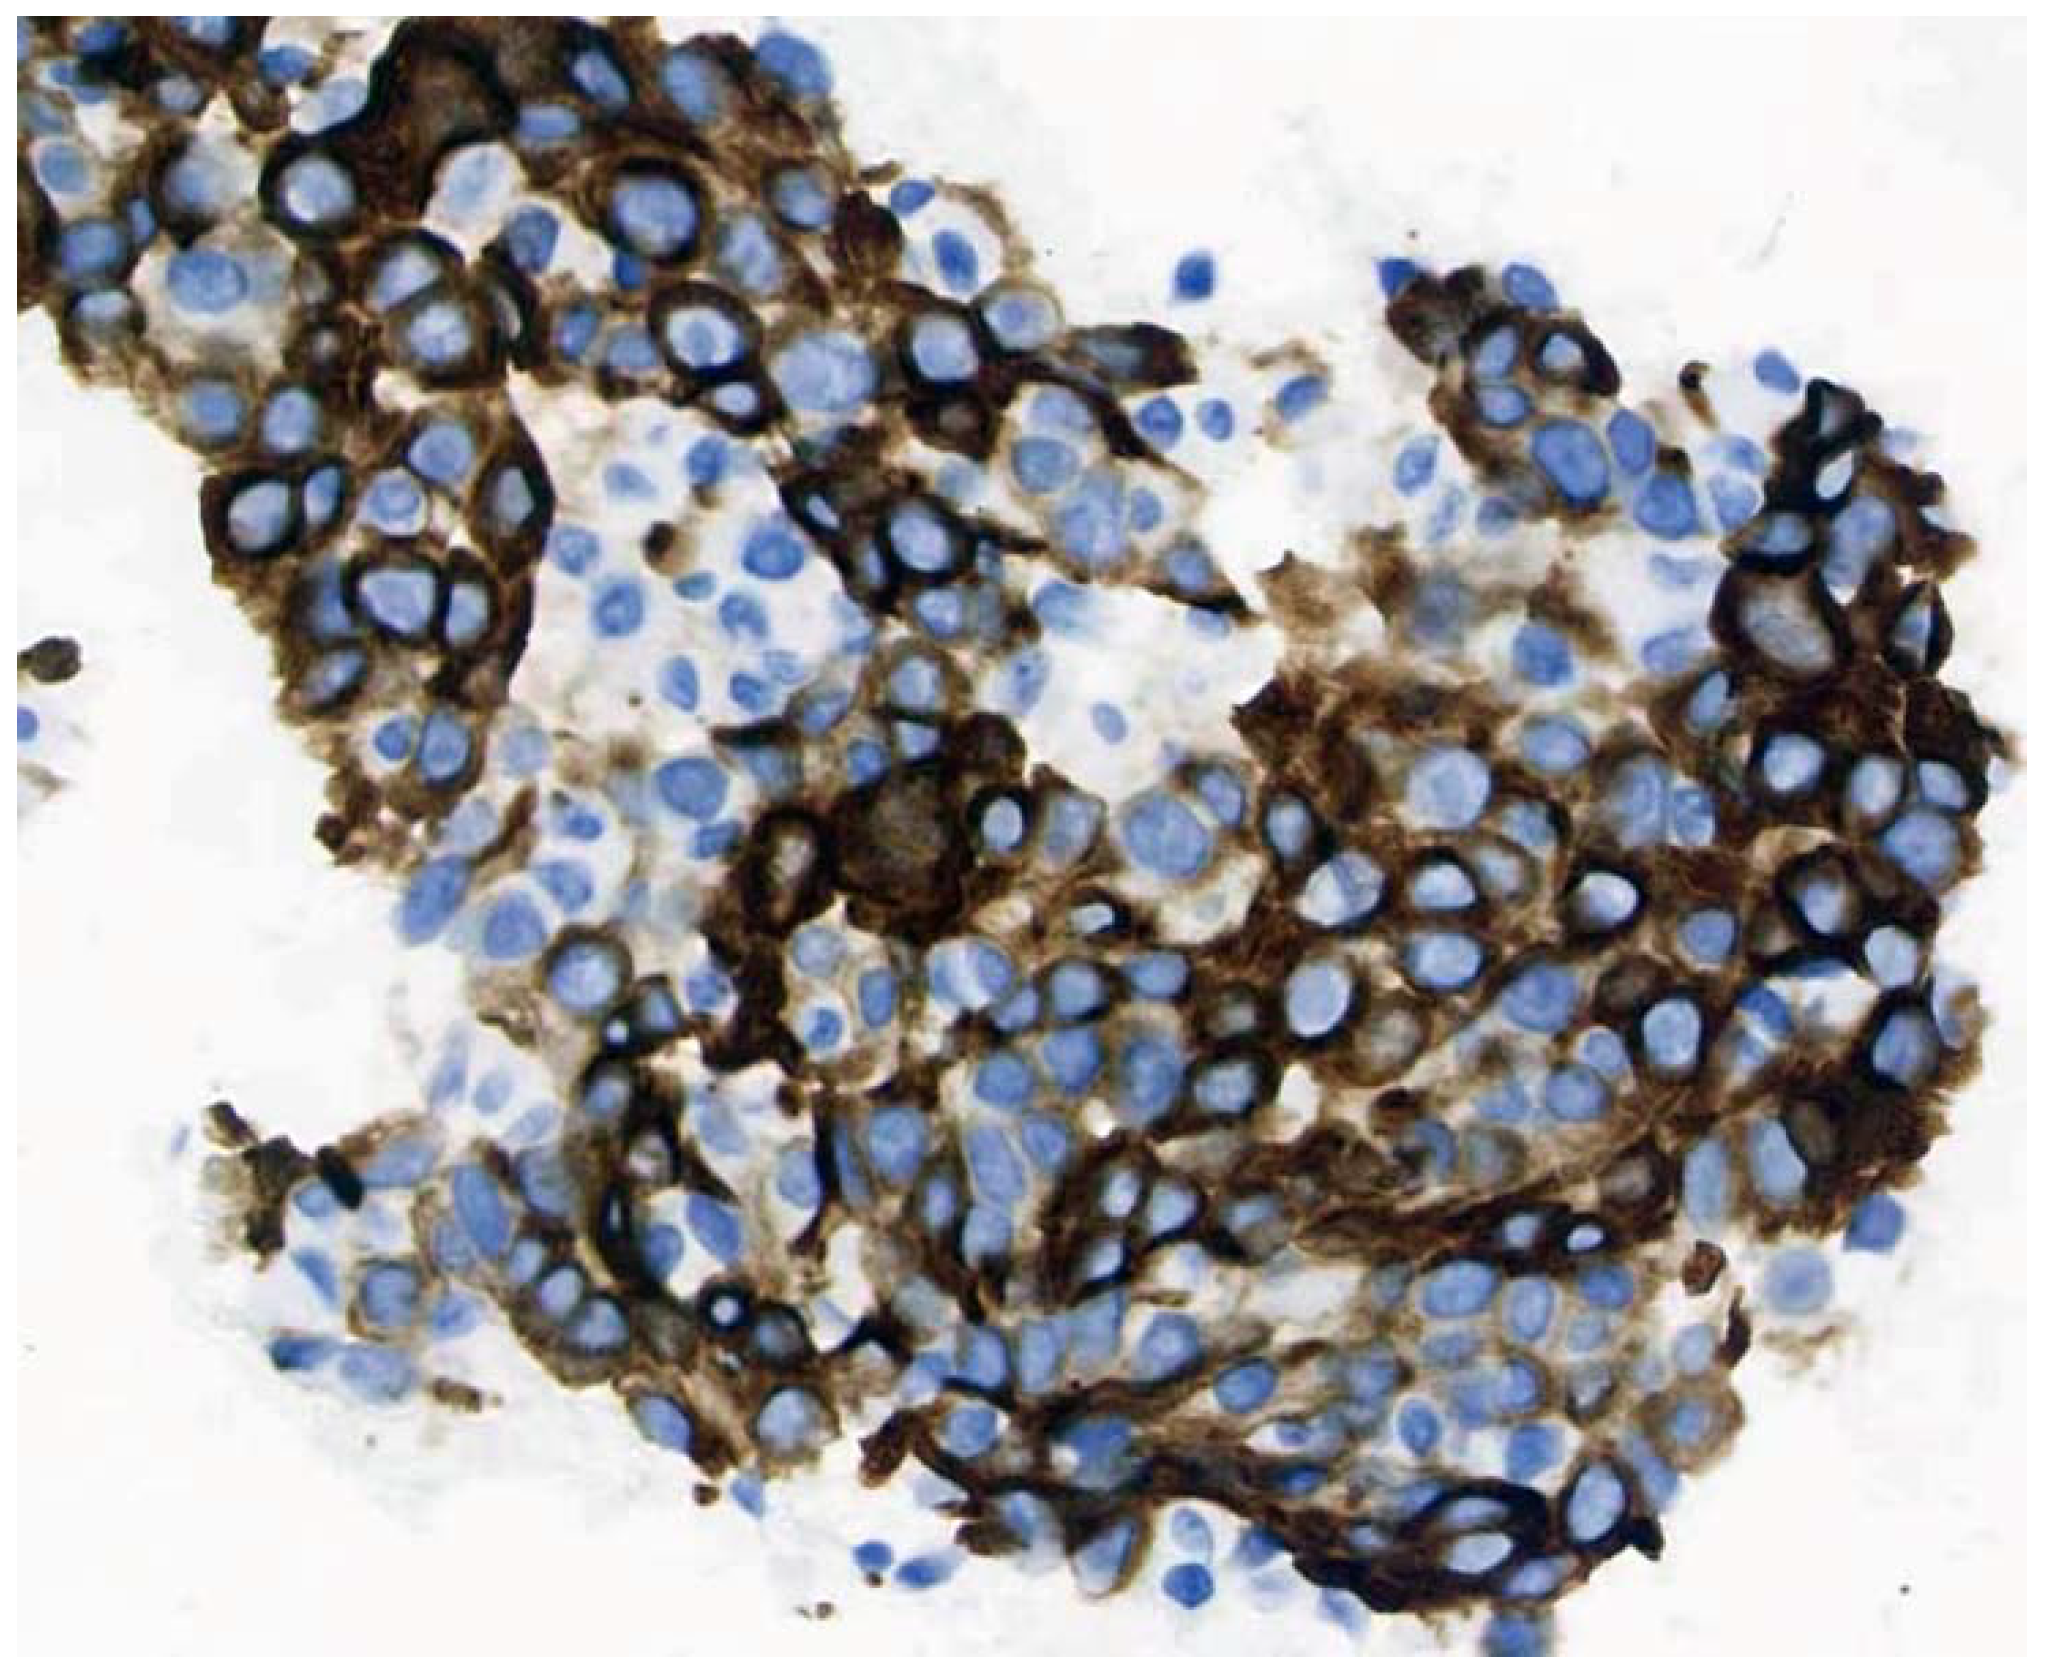

2. Case Presentation